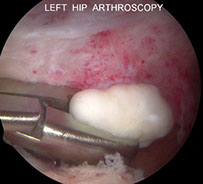

Synovial chondromatosis (osteochondromatosis)

Monarthritic dz c multiple metaplastic hyaline nodules within the articular space found just beneath the synovial lining cells (which were previously sublining cells of the synovium); affecting primarily the larger joints (hip, knee, shoulder)

- large age range; M>F

Pt presents c gradual onset of pain and "locking" of joints, with evidence of possible joint effusion

- the synovial surface is grossly hypertrophied c lots of little nodules

- in the nodules, chondrocytes arrange in clusters along the periphery

-- malignancy assoc c the loss of these clusters and more dispersed chondrocytes and the presence of spindle cells

-- in early dz the nodules are small and entirely cartilagenous

-- in late dz, large nodules occupy enlarged villi and the cartilage undergoes ossification (hence osteochondromatosis) and break free and float around the synovium (loose bodies)

- moderate atypia (binucleation and hyperchromasia) is common and not necessarily indicative of high grade

Synovial osteochondromatosis is when these nodules form by means of endochondral ossification

Imaging: multiple circumscribed opaque calcifications assoc c erosion of articular margins on xray

- CT/MRI shows signal voids w/in membrane (may be necessary if xray normal)

Gene: FN1::ACVR2A found in ~1/2 of cases, confirming the neoplastic nature of this disease

Tx: Synovectomy (in the intrasynovial dz phase); in the inactive phase, joint body excision is sufficient without synovectomy

Synovial chondromatosis